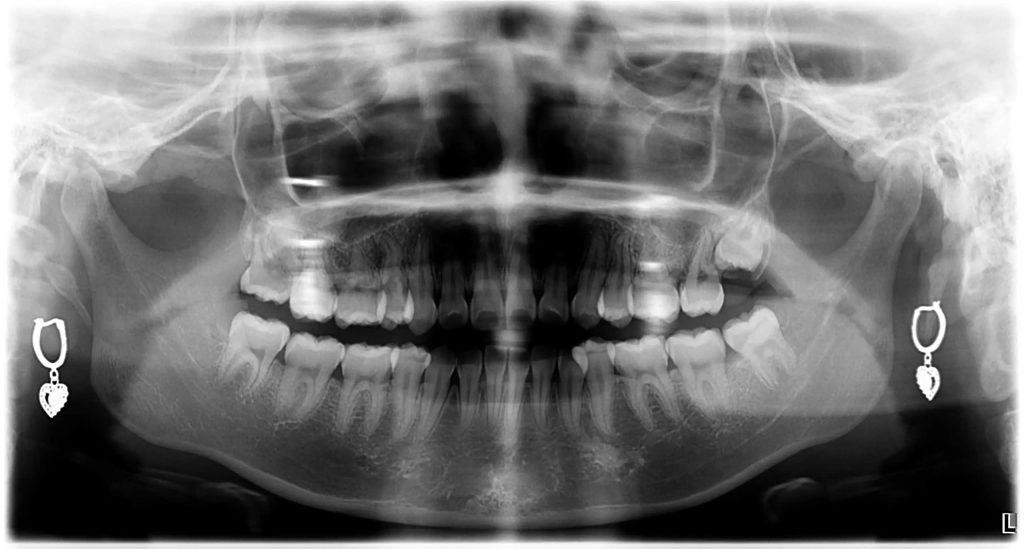

Khi hàm không đủ chỗ cho răng khôn mọc lên như bình thường, điều này có thể gây ra nhiều vấn đề cho sức khỏe răng miệng. Răng khôn có thể mọc ở nhiều góc độ khác nhau trong hàm, tạo ra hiện tượng răng mọc chen chúc, hoặc thậm chí mọc lệch và tạo ra các vấn đề:

- Vẫn nằm ẩn hoàn toàn trong nướu: nếu răng khôn bị mắc kẹt trong hàm. Điều này có thể dẫn đến nhiễm trùng hoặc tạo thành u nang gây tổn thương chân răng và các cấu trúc nâng đỡ răng khác.

- Nhú 1 phần lên khỏi nướu: khu vực răng khôn mọc thường khó nhìn thấy. Do đó, việc vệ sinh khó khăn, tạo điều kiện cho vi khuẩn phát triển, gây ra bệnh nướu răng và nhiễm trùng răng miệng.

- Mọc chen chúc: nếu khung hàm không có đủ chỗ để răng khôn phát triển bình thường, răng khôn có khả năng mọc chen chúc hoặc làm hỏng các răng lân cận, khiến các răng khác lung lay, tiêu xương hoặc mất răng.